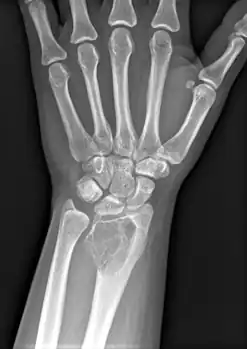

On X-ray, giant-cell tumors (GCTs) are lytic/lucent lesions that have an epiphyseal location and grow to the articular surface of the involved bone.[11] Radiologically the tumors may show characteristic 'soap bubble' appearance.[12] They are distinguishable from other bony tumors in that GCTs usually have a nonsclerotic and sharply defined border. About 5% of giant-cell tumors metastasize, usually to a lung, which may be benign metastasis,[13] when the diagnosis of giant-cell tumor is suspected, a chest X-ray or computed tomography may be needed. MRI can be used to assess intramedullary and soft tissue extension.

Front view X-ray. A well-defined expansile lesion in radius near wrist